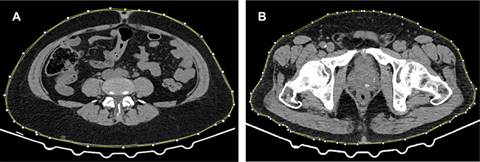

Posteriormente mediante el programa Image J se calculó el área de grasa visceral (AV) y subcutánea (AS), midiendo las densidades entre -190 y -30 UH (Figura 1). Para el cálculo de tejido adiposo en los diferentes compartimentos (subcutáneo y visceral) se ha demostrado que un solo cálculo en un corte axial a nivel umbilical es suficiente como muestra.6 Por último, se calculó la circunferencia para cintura y cadera de cada grupo (Figura 2).

Figura 1: Cálculo de áreas mediante el programa Image J en cortes axiales de tomografía computarizada donde resaltan los valores de atenuación correspondientes a las densidades grasas. A) Área de grasa total. B) Área de grasa subcutánea.